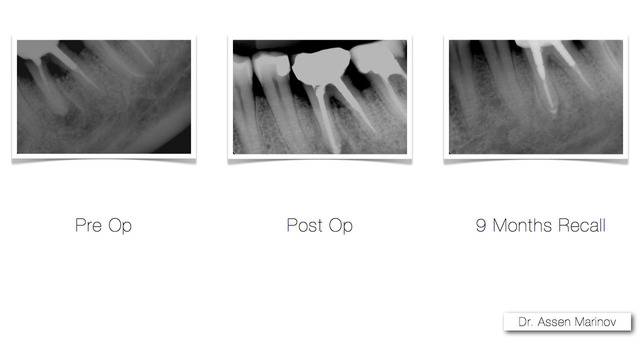

Пациентът дойде при нас с болка и подуване, причина за която е зъбен гранулом. Лечението на гранулома бе проведено без отстраняване на металокерамичната коронка. С помощта на оперативния микроскоп контролът по време на лечение е максимален. Това дава възможност за цялостно почистване на каналите и екзактното им запълване.

Лечението бе проведено в две посещения. На рентгеновата снимка, направена след девет месеца, се вижда пълен оздравителен процес.